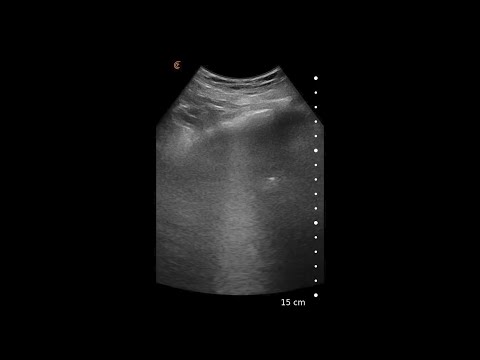

Webinar Covid-19 #2 – The role of Point of Care and lung ultrasound